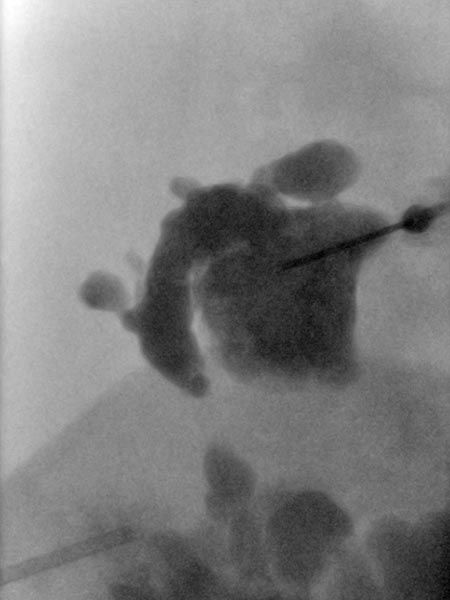

Overview X-ray in the area of the right pelvic crest after injection of contrast medium via the needle directly located in the lymphatic malformation. Large parts of the lymphatic malformation are contrasted from this needle position, representing an optimal needle position for sclerotherapy.